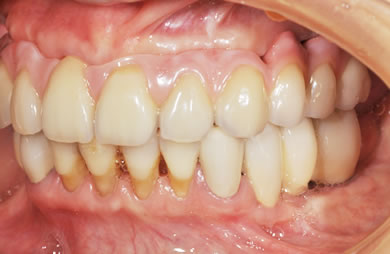

骨再生スピードインプラント治療+AGC連結セラミック治療

| 主訴 | 他院で骨の量が足りずインプラントは難しいと言われ、入れ歯を使用していたが、やはりインプラント治療をうけたい。 | ||||||||||||||||||||||||||||||||

| 治療方針 | 上顎の歯周組織がかなり侵襲されているため、ソケットリフト法にて骨を回復させ、機能的回復だけでなく審美的回復も行うためにAGCハイブリッド連結ブリッジにて補綴処置を行う。 | ||||||||||||||||||||||||||||||||

| 治療内容 | インプラント12本(ソケットリフト+抜歯即日スピードインプラント)、ハイブリッドセラミック8本、AGCハイブリッドセラミック連結ブリッジ1装置、テンポラリーインプラント2本、遊離歯肉移植術 | ||||||||||||||||||||||||||||||||